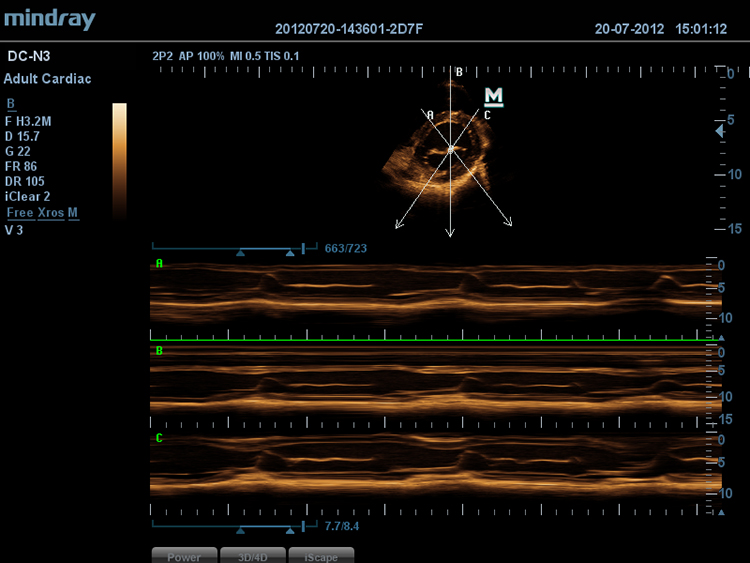

Free Xros MTM

–ü–æ–∑–≤–æ–ª—è–µ—Ç –ø–æ–ª—É—á–∏—Ç—å —Ç–æ—á–Ω—ã–µ –∞–Ω–∞—Ç–æ–º–∏—á–µ—Å–∫–∏–µ –∏–∑–º–µ—Ä–µ–Ω–∏—è –ø–æ—Å—Ä–µ–¥—Å—Ç–≤–æ–º —Å–≤–æ–±–æ–¥–Ω–æ–≥–æ —Ä–∞–∑–º–µ—â–µ–Ω–∏—è –ª–∏–Ω–∏–π –ú-—Ä–µ–∂–∏–º–∞ –ø–æ–¥ –ª—é–±—ã–º —É–≥–ª–æ–º. –û–ø—Ç–∏–º–∞–ª—å–Ω–æ–µ –∫–∞—á–µ—Å—Ç–≤–æ –∏–∑–æ–±—Ä–∞–∂–µ–Ω–∏—è –¥–æ—Å—Ç–∏–≥–∞–µ—Ç—Å—è —Å –ø–æ–º–æ—â—å—é –æ–¥–Ω–æ–≤—Ä–µ–º–µ–Ω–Ω–æ–≥–æ –∏—Å–ø–æ–ª—å–∑–æ–≤–∞–Ω–∏—è –¥–æ 3 –ª–∏–Ω–∏–π –ú-—Ä–µ–∂–∏–º–∞.

Free Xros CMTM

–ü–æ–∑–≤–æ–ª—è–µ—Ç –ø–æ–ª—É—á–∏—Ç—å –ø–æ–ª–Ω—É—é –∏–Ω—Ñ–æ—Ä–º–∞—Ü–∏—é –æ –¥–≤–∏–∂–µ–Ω–∏–∏ —Å–µ—Ä–¥–µ—á–Ω–æ–π –º—ã—à—Ü—ã –≤ —Ä–∞–∑–ª–∏—á–Ω—ã—Ö —Ñ–∞–∑–∞—Ö —Å–æ–∫—Ä–∞—â–µ–Ω–∏—è –∏ –æ–¥–Ω–æ–≤—Ä–µ–º–µ–Ω–Ω–æ –æ–ø—Ä–µ–¥–µ–ª—è—Ç—å —Å—Ç–µ–ø–µ–Ω—å —Å–∏–Ω—Ö—Ä–æ–Ω–∏–∑–∞—Ü–∏–∏ –º–∏–æ–∫–∞—Ä–¥–∞. –¢–æ—á–Ω–æ—Å—Ç—å —Ä–µ–∑—É–ª—å—Ç–∞—Ç–æ–≤ –æ–±–µ—Å–ø–µ—á–∏–≤–∞–µ—Ç—Å—è –≤—ã—Å–æ–∫–æ–π —á–∞—Å—Ç–æ—Ç–æ–π –∫–∞–¥—Ä–æ–≤.